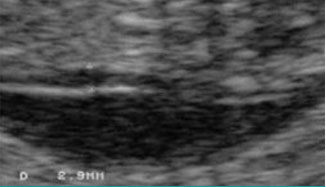

寶寶頸后透明帶為6毫米,具有很高的唐氏綜合癥以及其它染色體、遺傳綜合癥和心臟問題的風(fēng)險。

安琪兒專家溫馨提示:如果nt檢測結(jié)果超出標(biāo)準(zhǔn)值范圍,建議孕婦進(jìn)行后續(xù)的排畸檢查,以進(jìn)一步確認(rèn)胎兒異常的風(fēng)險,以便及早采取應(yīng)對措施。